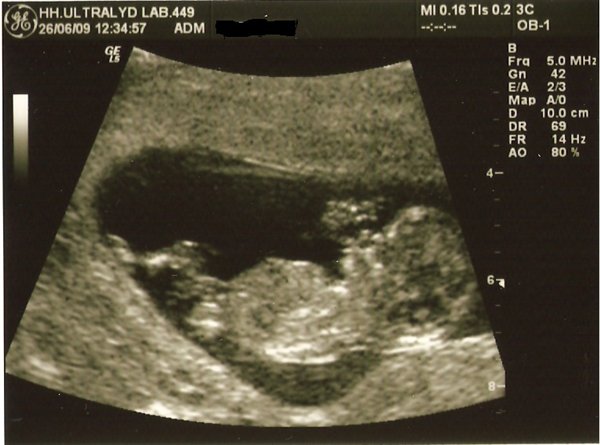

Jeg var til nf i dag! iih, hvor var det spændende og dejligt at se den lille.

Alt så fint ud og synes at billederne blev rigtig flotte

Terminen blev rykket et par dage fra 10.01.10 til 06.01.10, så er 12+2 uger henne

Vi har ikke fået svar fra doubletesten endnu, så har ikke fået endeligt svar.. Men udfra skanningen så alt fint ud, husker ikke helt, men det var ca. 1:5700, så det var SUPER.